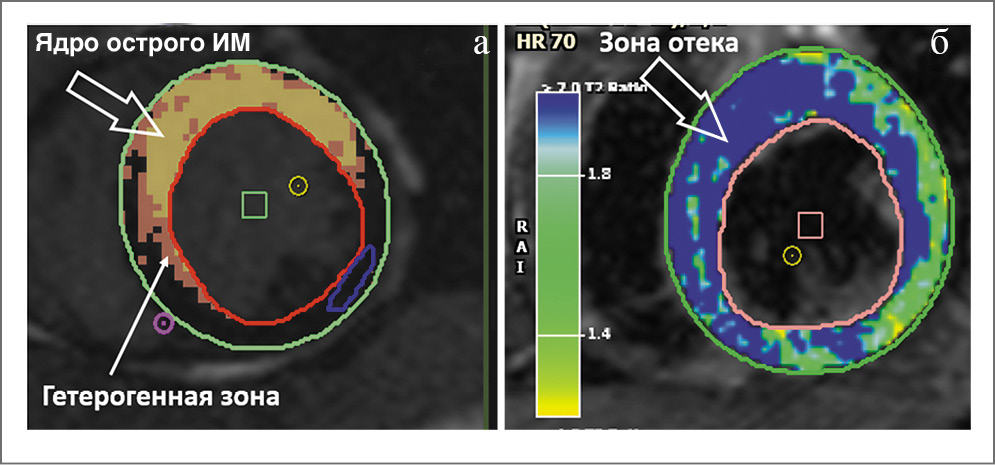

Размер инфаркта определяется как объем (или масса) зоны острого очагового повреждения (а в последующем фиброза), накапливающей контрастное вещество. Зона инфаркта является морфологически неоднородной. В ее структуру входит ядро, представленное в остром периоде ИМ некротизированными кардиомиоцитами, а в последующем – фиброзной тканью, и гетерогенная зона, состоящая из некротизированных, находящихся в состоянии ишемии и интактных кардиомиоцитов [18–20]. Результаты электрофизиологических исследований и гистологического анализа гетерогенной зоны показали одновременное сосуществование в этой зоне процессов апоптоза и активной репарации [18]. На изображениях МРТ с отсроченным контрастированием гетерогенная зона представляет собой область, где ИС составляет менее 50% от максимальной ИС в зоне инфаркта, но больше максимальной ИС интактной зоны (рис. 4, 5).

Рис. 5. Тканевой анализ изображений в фазу отсроченного контрастирования (а) и на Т2-ВИ (б)

Если повреждение коронарного микроциркуляторного русла в результате ИМпST достаточно велико и целостность сосудов нарушена, то возникает экстравазация эритроцитов в миокард, или ИМК. МР-оценка ИМК осуществляется с помощью Т2*-ВИ или Т2*-картирования, чувствительных к выявлению продуктов распада гемоглобина [1]. По аналогии с МСО на T2*-ВИ (T2*-картах) продукты распада гемоглобина в миокарде визуализируются в виде гипоинтенсивных ядер в зоне ИМ [22].